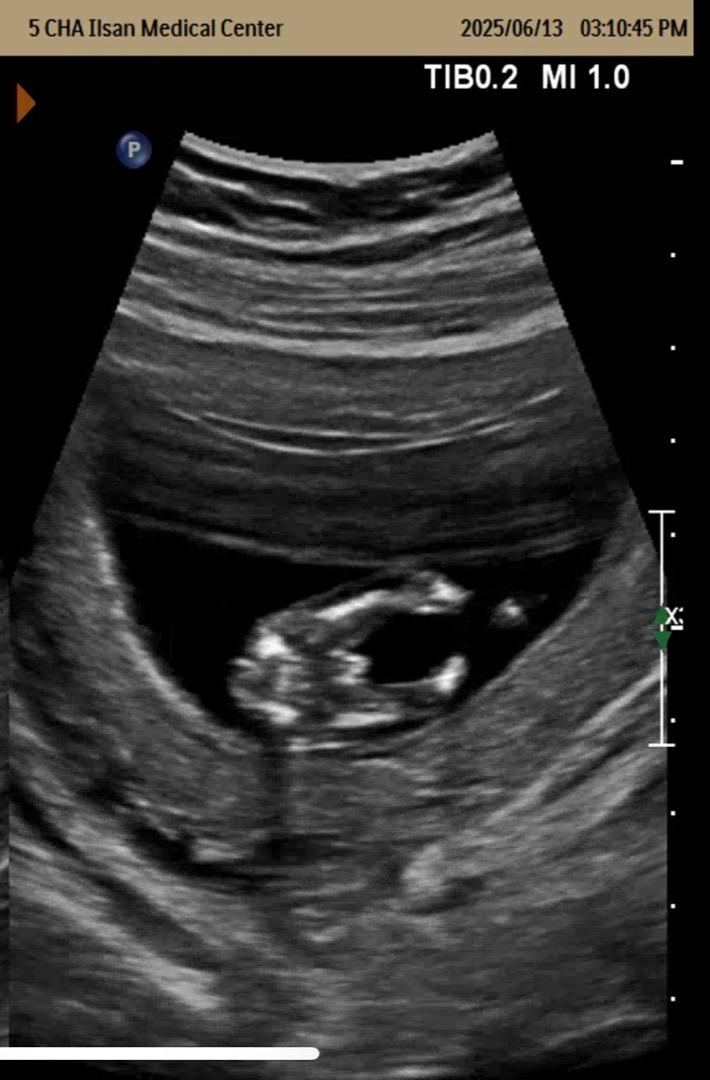

12주 4일차 아기 성별 한번 봐주세요ㅎㅎ

다른분들 글 보고 어떻게 벌써 아는거지? 했었는데 저도 못참고 올려보게 되네요 ㅎㅎ.. 저.. 가랑이 사이의 저것.. 🌶️가 맞을까요..? ㅋㅋ 병원에선 초음파 선생님도 교수님도 입꾹닫이셔서 물어볼 엄두도 못냈네요 ㅎㅎ..